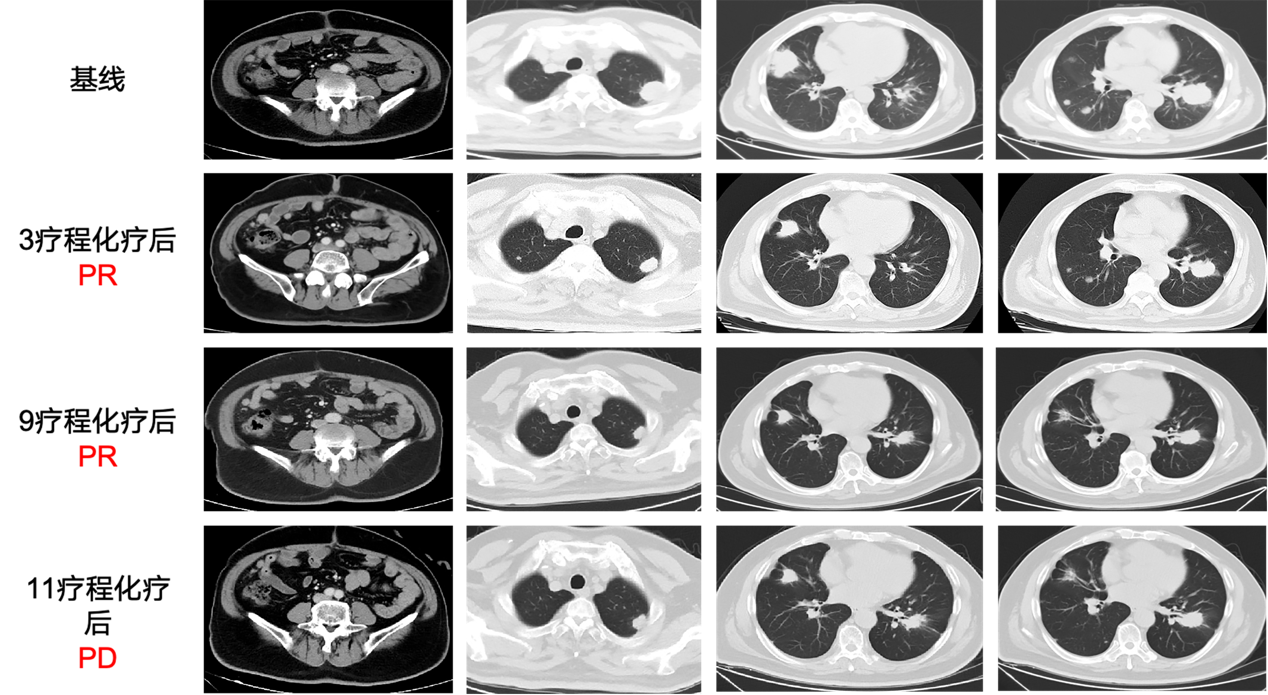

三线治疗

2025.01

因排便排气停止伴有恶心呕吐1天,明确诊断乙状结肠癌伴有肠梗阻,CT显示双肺多发转移瘤(0.5-4.6cm),纵膈内见多发略肿大淋巴结,腹膜多发转移。肿瘤标志物: CEA 196.34ng/ml, CA242 94.3U/ml, CA199 68.1U/ml。基因检测: RAS/RAF野生, MSS, TP53基因突变, PIK3CA基因突变, TMB 3.84个突变/Mb。

入组IIT临床试验:呋喹替尼联合PD-1单抗及西达本胺在难治性MSS型转移性结直肠癌中疗效和安全性的Ⅱ期临床研究,行西达本胺(30mg Biw)联合信迪利单抗(200mg,Q3w)和呋喹替尼(5mg qd,d1-14,Q3w)联合方案(CAP)治疗。

2024.03

复查CT提示肺部病灶及肝内转移灶,较前均明显缩小,疗效评估PR。

2025.06

复查CT提示肺部病灶及肝内转移灶,较前均明显缩小,疗效评估PR,患者持续规律CAP方案治疗,定期随访。

图片5.png

图5 影像学评估

治疗小结

本例患者的诊疗实践,为晚期MSS/pMMR型患者3-4线治疗提供了重要临床参考,同时有力印证了西达本胺联合方案的临床价值。本例患者为MSS/pMMR、RAS/RAF野生型转移性直肠癌患者, 经姑息性手术后一线化疗联合西妥昔单抗方案、二线化疗联合贝伐珠单抗治疗失败后,采用CAP方案(西达本胺+信迪利单抗+呋喹替尼)治疗后持续PR,截止目前PFS长达12个月。作为全球首个口服亚型选择性组蛋白去乙酰化酶抑制剂(HDACi), 西达本胺联合信迪利单抗和呋喹替尼分别从重塑肿瘤免疫微环境、激活机体抗肿瘤免疫应答、改善肿瘤血管异常等维度持续发力,为这类患者临床治疗选择提供了新思路。

本例患者姑息手术后晚期一线接受11个周期FOLFOX+西妥昔单抗方案后肺部病灶进展,二线接受仅接受了3个周期FOLFIRI+贝伐珠单抗肺部病灶再次进展,入组IIT临床试验尝试了西达本胺联合信迪利单抗和呋喹替尼的CAP方案,三种药物可发挥协同增效作用,肺部持续缩小,肿瘤标志物持续下降,PFS超过12个月,给患者带来了生的希望。且呋喹替尼、西达本胺为口服类药物,减少患者住院频次和缩短住院时间,提升用药便利性和患者依从性,进而提高疗效。